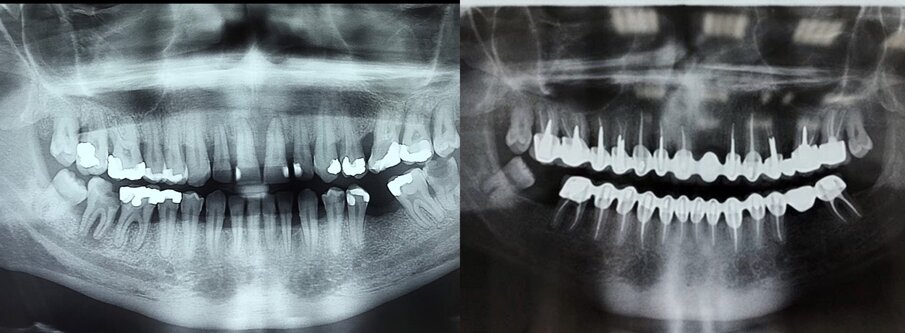

Pacijent starosti 29 godina, s agresivnom formom parodontitisa. Pacijent je u trajanju od 2 godine lečen nehirurškom, a zatim i hirurškom terapijom oboljenja parodoncijuma uz primenu preparata GelCide. Nakon 2 godine, pacijent je protetski rehabilitovan fiksnim protetskim radom.